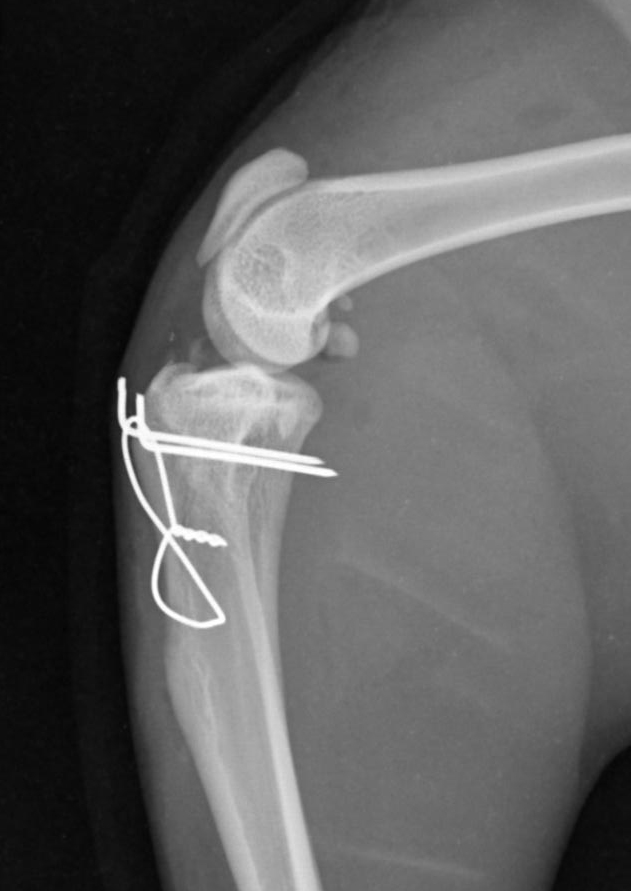

Mobile Orthopaedic & Soft-Tissue Surgery for Small Animals

Offering complex orthopaedic, soft-tissue, and thoracic procedures directly within your practice, providing patients with high-quality surgical care in a familiar and low-stress environment.